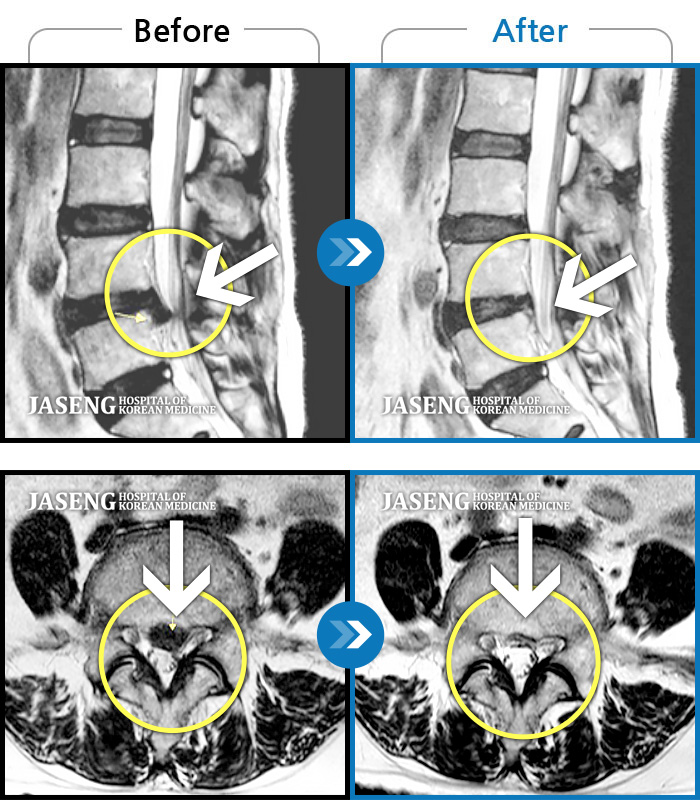

Before

After

허리통증, 왼쪽 다리 저림 및 통증

2018.01.18 ~ 2019.08.09